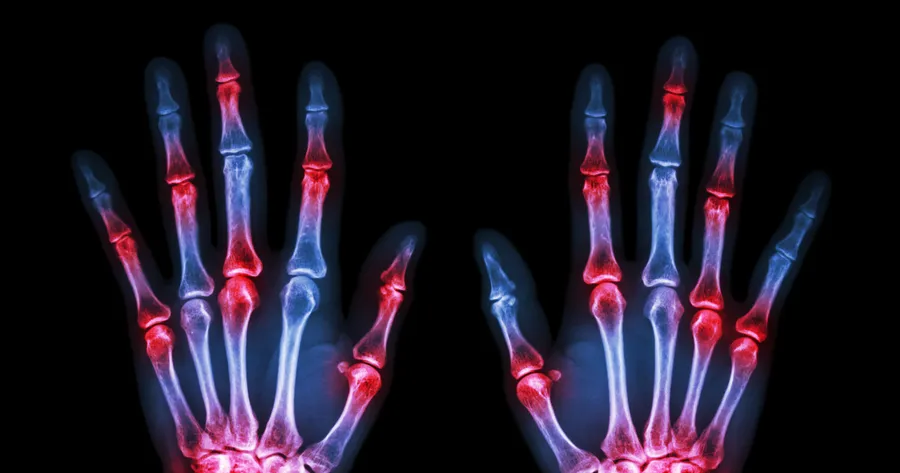

While the best-known symptom of rheumatoid arthritis might be joint pain, this condition is so much more than everyday pain. It’s a systemic autoimmune disease that typically occurs in joints on both sides of the body. And over time, as different areas of the body become inflamed, joint damage can happen.

It’s important to note that this is a symptom with a unique trait. Unlike some other forms of arthritis, joint pain that’s the product of rheumatoid arthritis typically appears on both sides of the body⁴. For example, if you have joint pain in one knee, it’s likely to occur in the opposite knee too.

RA can cause minor swelling in your joints when it’s in its earliest stages. Your joints may appear a bit larger than normal, and they may feel warm to the touch.

Any joint can experience this swelling, but remember that it will likely happen in both sides of the body simultaneously – for example, both hands will swell or both knees will swell. Swelling can happen when you experience a flare up⁶, or a surge in RA symptoms and inflammation. This can happen in the same joints repeatedly, or it can occur in different joints each time.